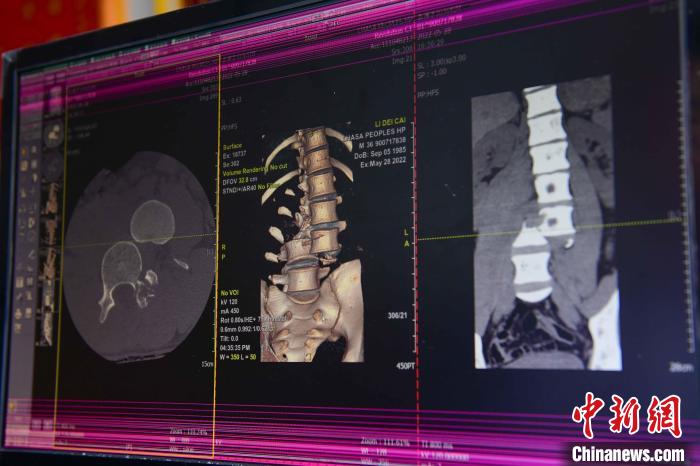

圖為(wei) 患者術前,腰3/4脊柱骨折伴脫位。 紮西曲措 攝

圖為(wei) 何蔚副主任醫師仔細翻閱患者CT片子。 貢嘎來鬆 攝

通道開通後,拉薩市人民醫院完成了兩(liang) 例脊柱創傷(shang) 截癱患者的救治。一例23歲的病患為(wei) 胸12椎體(ti) 爆裂骨折伴截癱,另一例36歲的病患腰椎體(ti) 骨折脫位伴雙下肢癱。按照脊髓損傷(shang) 救治綠色通道流程,術前充分快速完善相關(guan) 檢查,充分術前評估,向患者詳細交代手術風險,入院當天急診行手術治療。